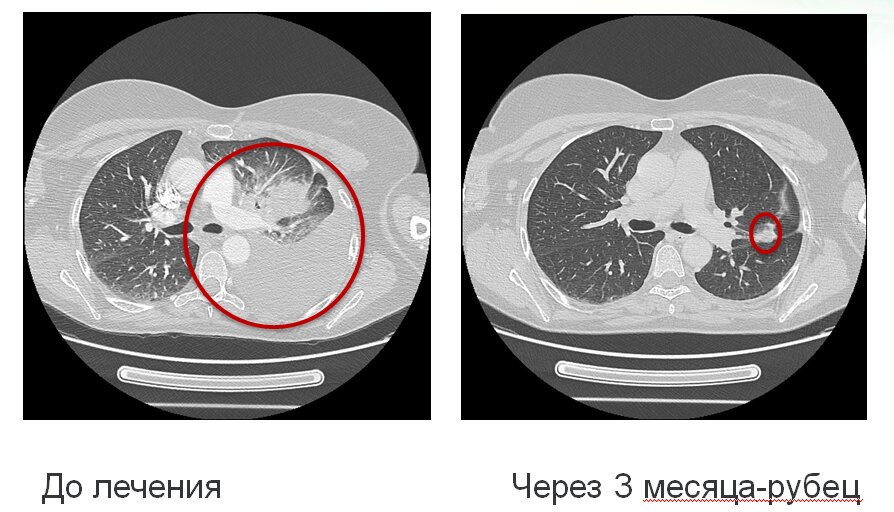

И, наконец, позвольте показать как выглядит результат лечения рака легкого таргетным препаратом кризотиниб при мутации ROS1:

Онкология шагнула далеко вперед! Проконсультируйтесь с вашим врачом personco@mail.ru!